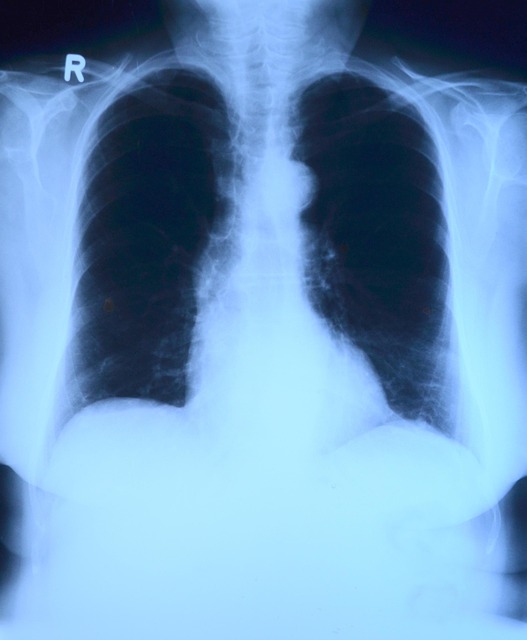

画像検査

風邪症状で画像検査を考える場合は、肺炎の除外が目的になります。

胸部レントゲンは1枚~2枚撮影であり、実費負担は約800円前後に収まります

胸部CTまで行う場合は追加で実費負担として3000円前後となります。(設置してあるCTの性能の良さでも変化します)